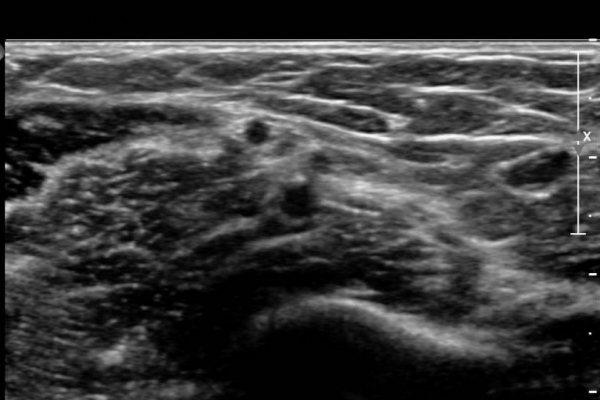

¾Æ·§ÆÈ¿¡¼­ Àü°ñ°£ ½Å°æºÎÀ§ Ⱦ´Ü¸é°Ë»ç»ó ¾öÁö ±¼±ÙÀÇ °í¿¡ÄÚ º¯¼ºÀÌ °üÂûµÇ°í  Àü°ñ°£µ¿¸Æ

ÁÖÀ§¿¡¼­ Á¾±« µî Ưº°ÇÑ ÀÌ»ó ¼Ò°ßÀÌ °üÂûµÇÁö ¾Ê´Â´Ù(»çÁø 1).